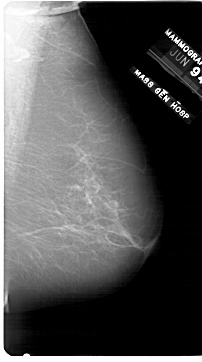

A_1750_1.RIGHT_MLO

RIGHT_CC LINES 6016 PIXELS_PER_LINE 3376 BITS_PER_PIXEL 12 RESOLUTION 43.5 NON_OVERLAY

RIGHT_MLO LINES 6871 PIXELS_PER_LINE 3826 BITS_PER_PIXEL 12 RESOLUTION 43.5 NON_OVERLAY